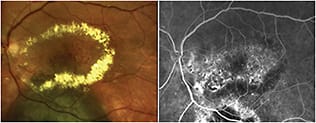

Figure 3. Color fundus photo (left) of an eye with AMD that was unresponsive to intravitreal pharmacotherapy, showing retinal exudation and scarring. A Navilas treatment plan (right) for grid laser maculopexy, based on retinal thickness map from an OCT scan of the same eye imported into the Navilas system, overlaid on the FA image, and aligned on the foveal center of the same eye. False color (red) shows retinal thickening.

Figure 4. Fluorescein angiogram (left) of the same eye in Figure 3, showing exudation and scarring. A Navilas treatment plan (right) for grid laser maculopexy based on the FA image.